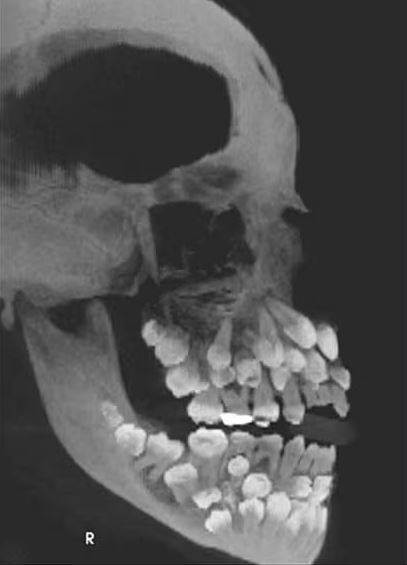

一名11歲的巴西女童因乳牙搖搖欲墜,到牙科診所看診,怎料醫生在拍完X光後,發現她嘴裡竟塞了81顆牙齒!

根據媒體《Chosun Biz》的報導,《美國齒顎矯正與顏面矯形學期刊》2011年曾刊登一起罕見病例,巴西一名11歲女童因想拔除一顆上排乳牙就醫,起初牙醫進行口腔檢查時並無異狀,誰知在照完X光後醫生大驚失色,因為女童嘴裡竟藏了18顆乳牙、32顆恆牙,以及31顆多生牙,一張小嘴共擁有多達81顆牙齒。